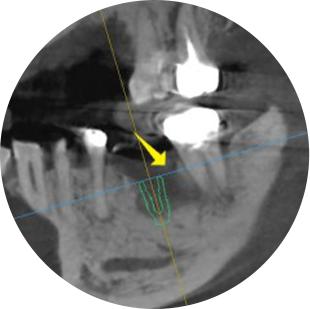

01신경손상을 막아주는 3D-CT3D-CT를 통해 신경손상의 원인을 사전에 차단삼성올바른치과는 부작용 걱정없이 임프란트 시술을 위하여 3D-CT를 이용하여 임플란트를 식립할 환자의 뼈의 상태를 정밀하게 분석하고, 신경관이 지나가는 미세한 부분까지 확인하여 신경손상의 원인을 사전에 차단하여 정확하고 안전하게 임플란트를 식립합니다.

02부작용을 줄이는 사전 시뮬레이션실제 환자의 얼굴뼈와 일치하는 영상으로 모의수술을 진행3차원 입체영상을 바탕으로 환자의 얼굴뼈와 일치하는 영상을 만들어 모의수술을 진행하여 환자에게 가장 적합한 수술방법을 찾아냅니다. CT장비를 이용하여 뼈의 0.1mm까지 분석하며 신경손상, 잇몸통증 등 수술중이나 수술후의 합병증과 불편함을 줄여 부작용없이 안전한 치료가 가능합니다.